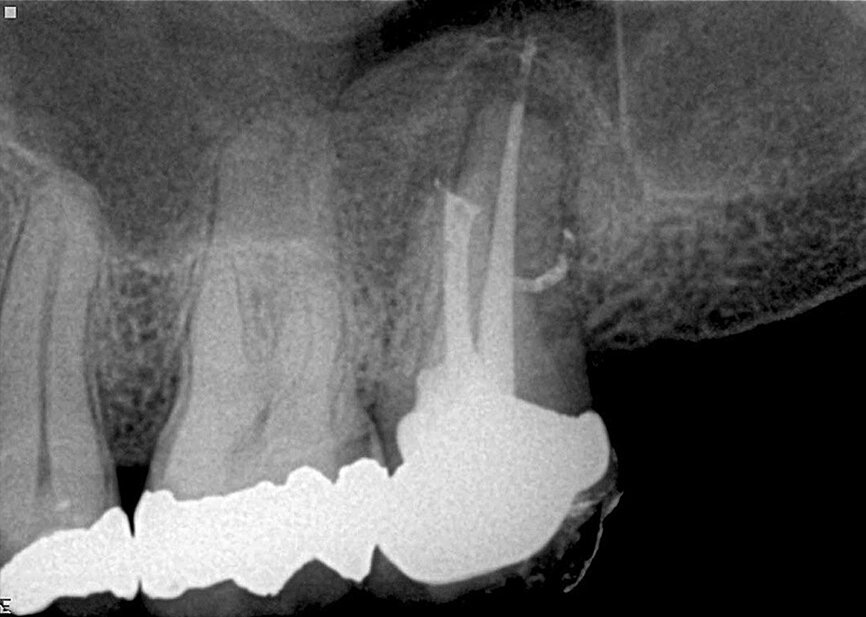

Fig. 5: The case was referred for retreatment due to the failure of the previous root canal therapy. Following the shaping (TF-adaptive) and cleaning (Sleiman protocol), and upon the challenging but successful search for the distal canal, a 3-D obturation was performed, which allows showing the isthmus between the mesial and distal canals as well as a very coronally located lateral canal in the palatal root.